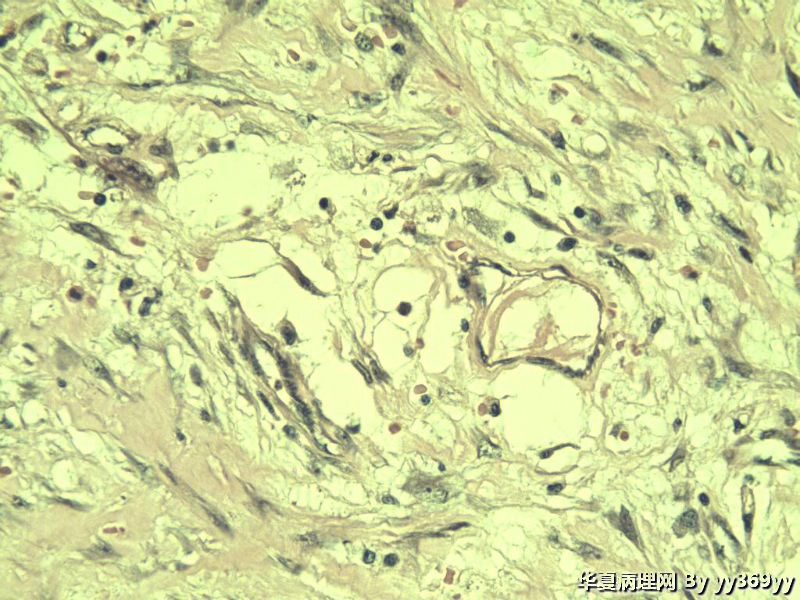

恶性的血管瘤??

男 30岁 小肠一段,肠管严重粘连可见一体积为 2.5 × 2 × 1.5 cm3的肿块,切面灰白,实性,质中

恶性的血管瘤??图1

肿块确切位置?图片颜色不正,需要考虑的有:脂肪坏死/腹腔纤维瘤病/炎性肌纤维母细胞瘤等。